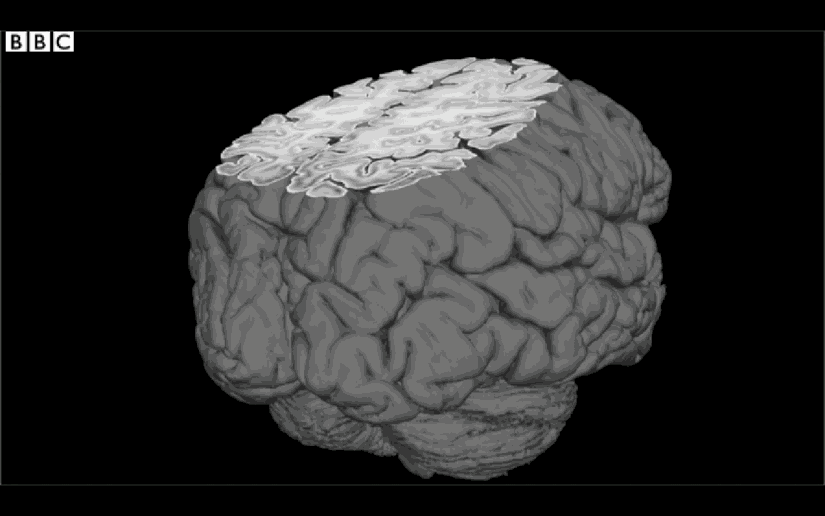

1. Kafamızın MRI görüntüsünün hızlandırılmış hali...